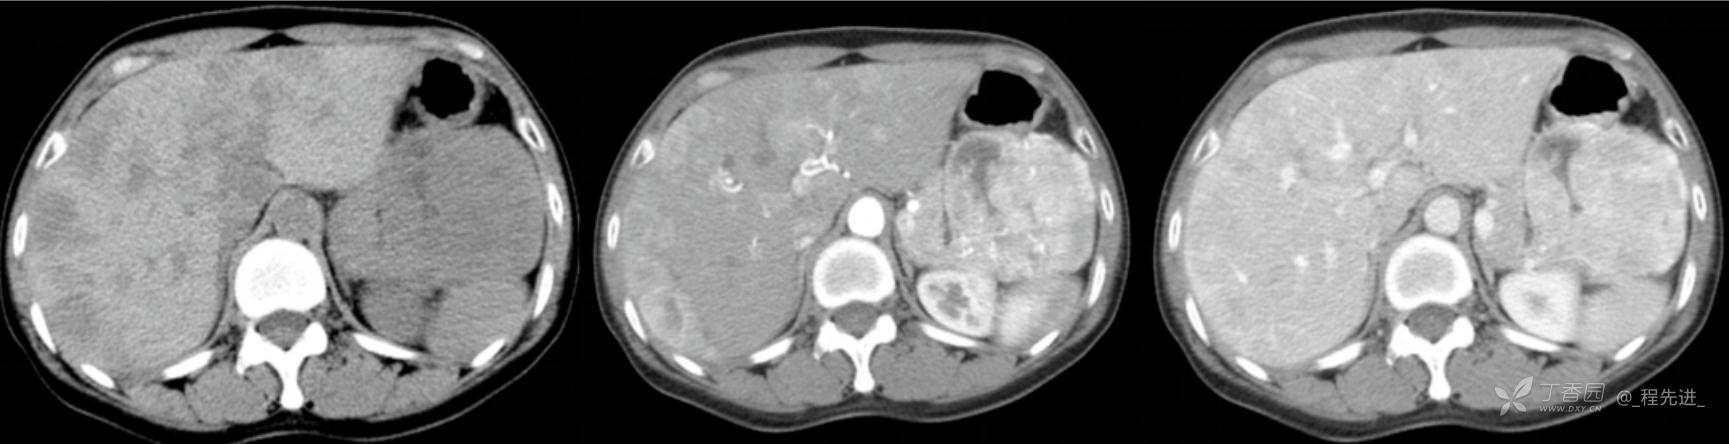

图像左边为平扫,中间的是动脉期,右边的是静脉期